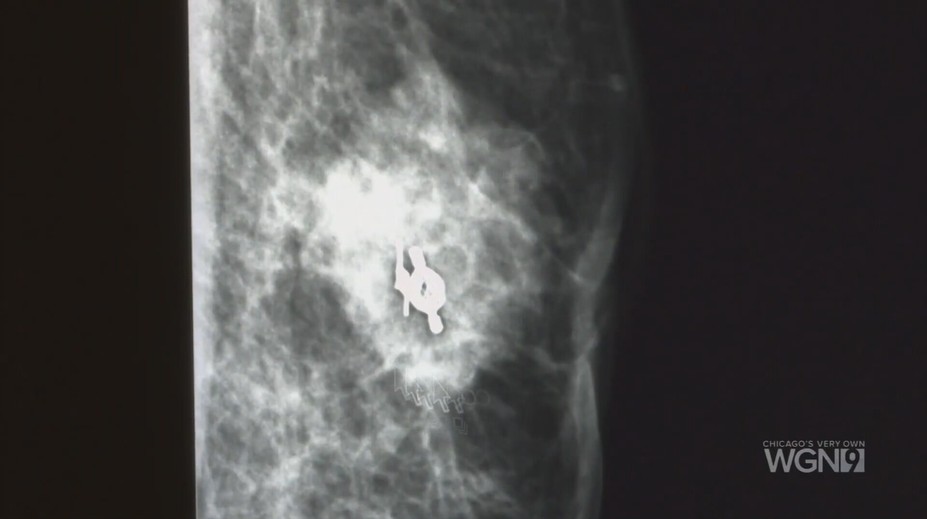

Nádor na prsníkoch neohrozuje len ženy. U mužov je ochorenie výrazne agresívnejšie Chantal R. Staruch 14. 10. 2025